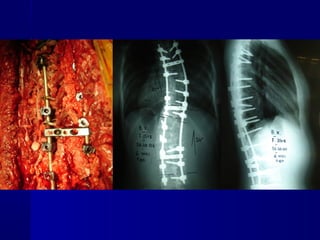

64. Ε. Φρ.Ε. Φρ.

ΘΘ –– 16+1016+10

ΘΘ66 - Θ- Θ1111 (Δ) 70(Δ) 70οο

ΘΘ1212 - Ο- Ο44 (Α) 52(Α) 52οο

King IIKing II